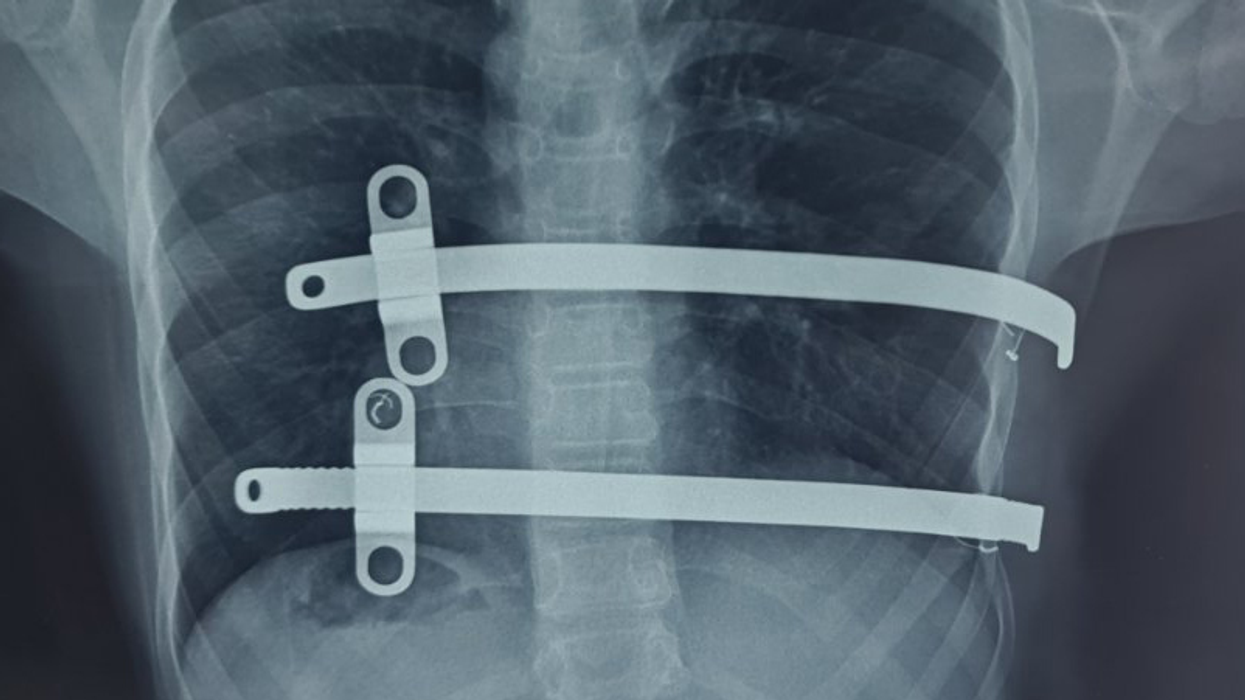

Bëhet fjalë për korrigjim të kafazit të kraharorit me Pectus Bar (pjesë metalike e vendosur në pjesën e përparme të gjoksit).